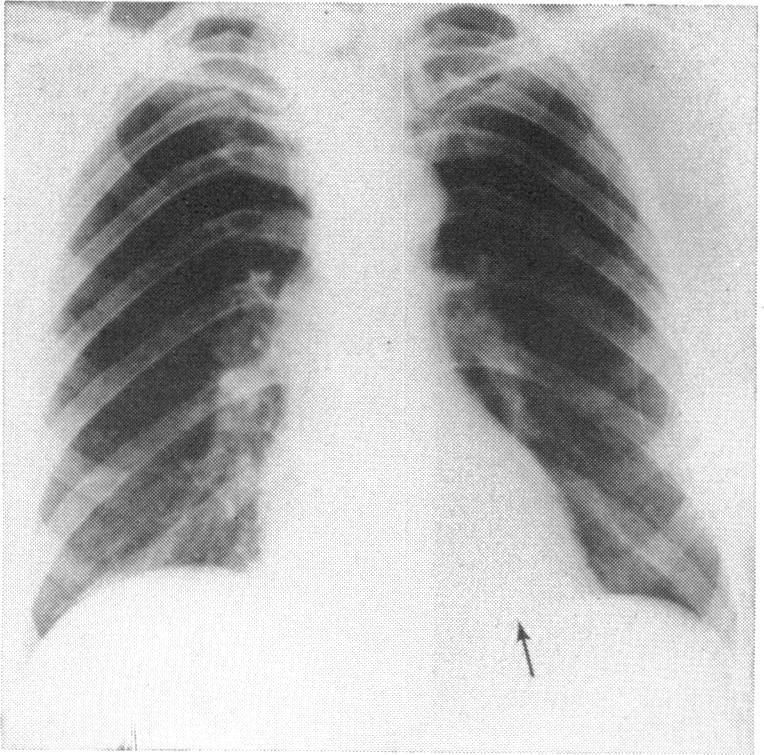

Transvenous pacing in presence of anomalous venous return to heart.

Br Heart J. 1972 Nov;34(11):1189-91. doi: 10.1136/hrt.34.11.1189.